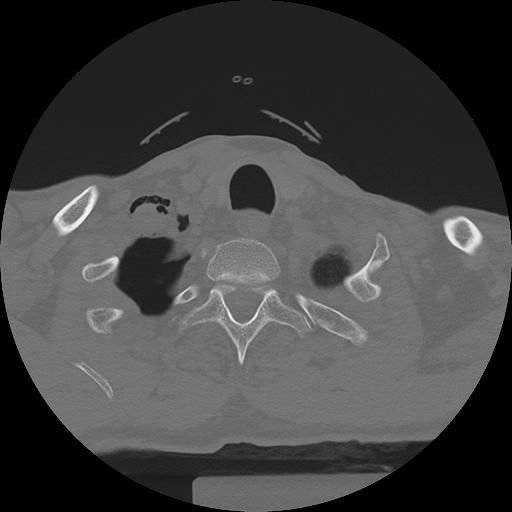

11 HUESO,,Axial,2.0,HUESO,,